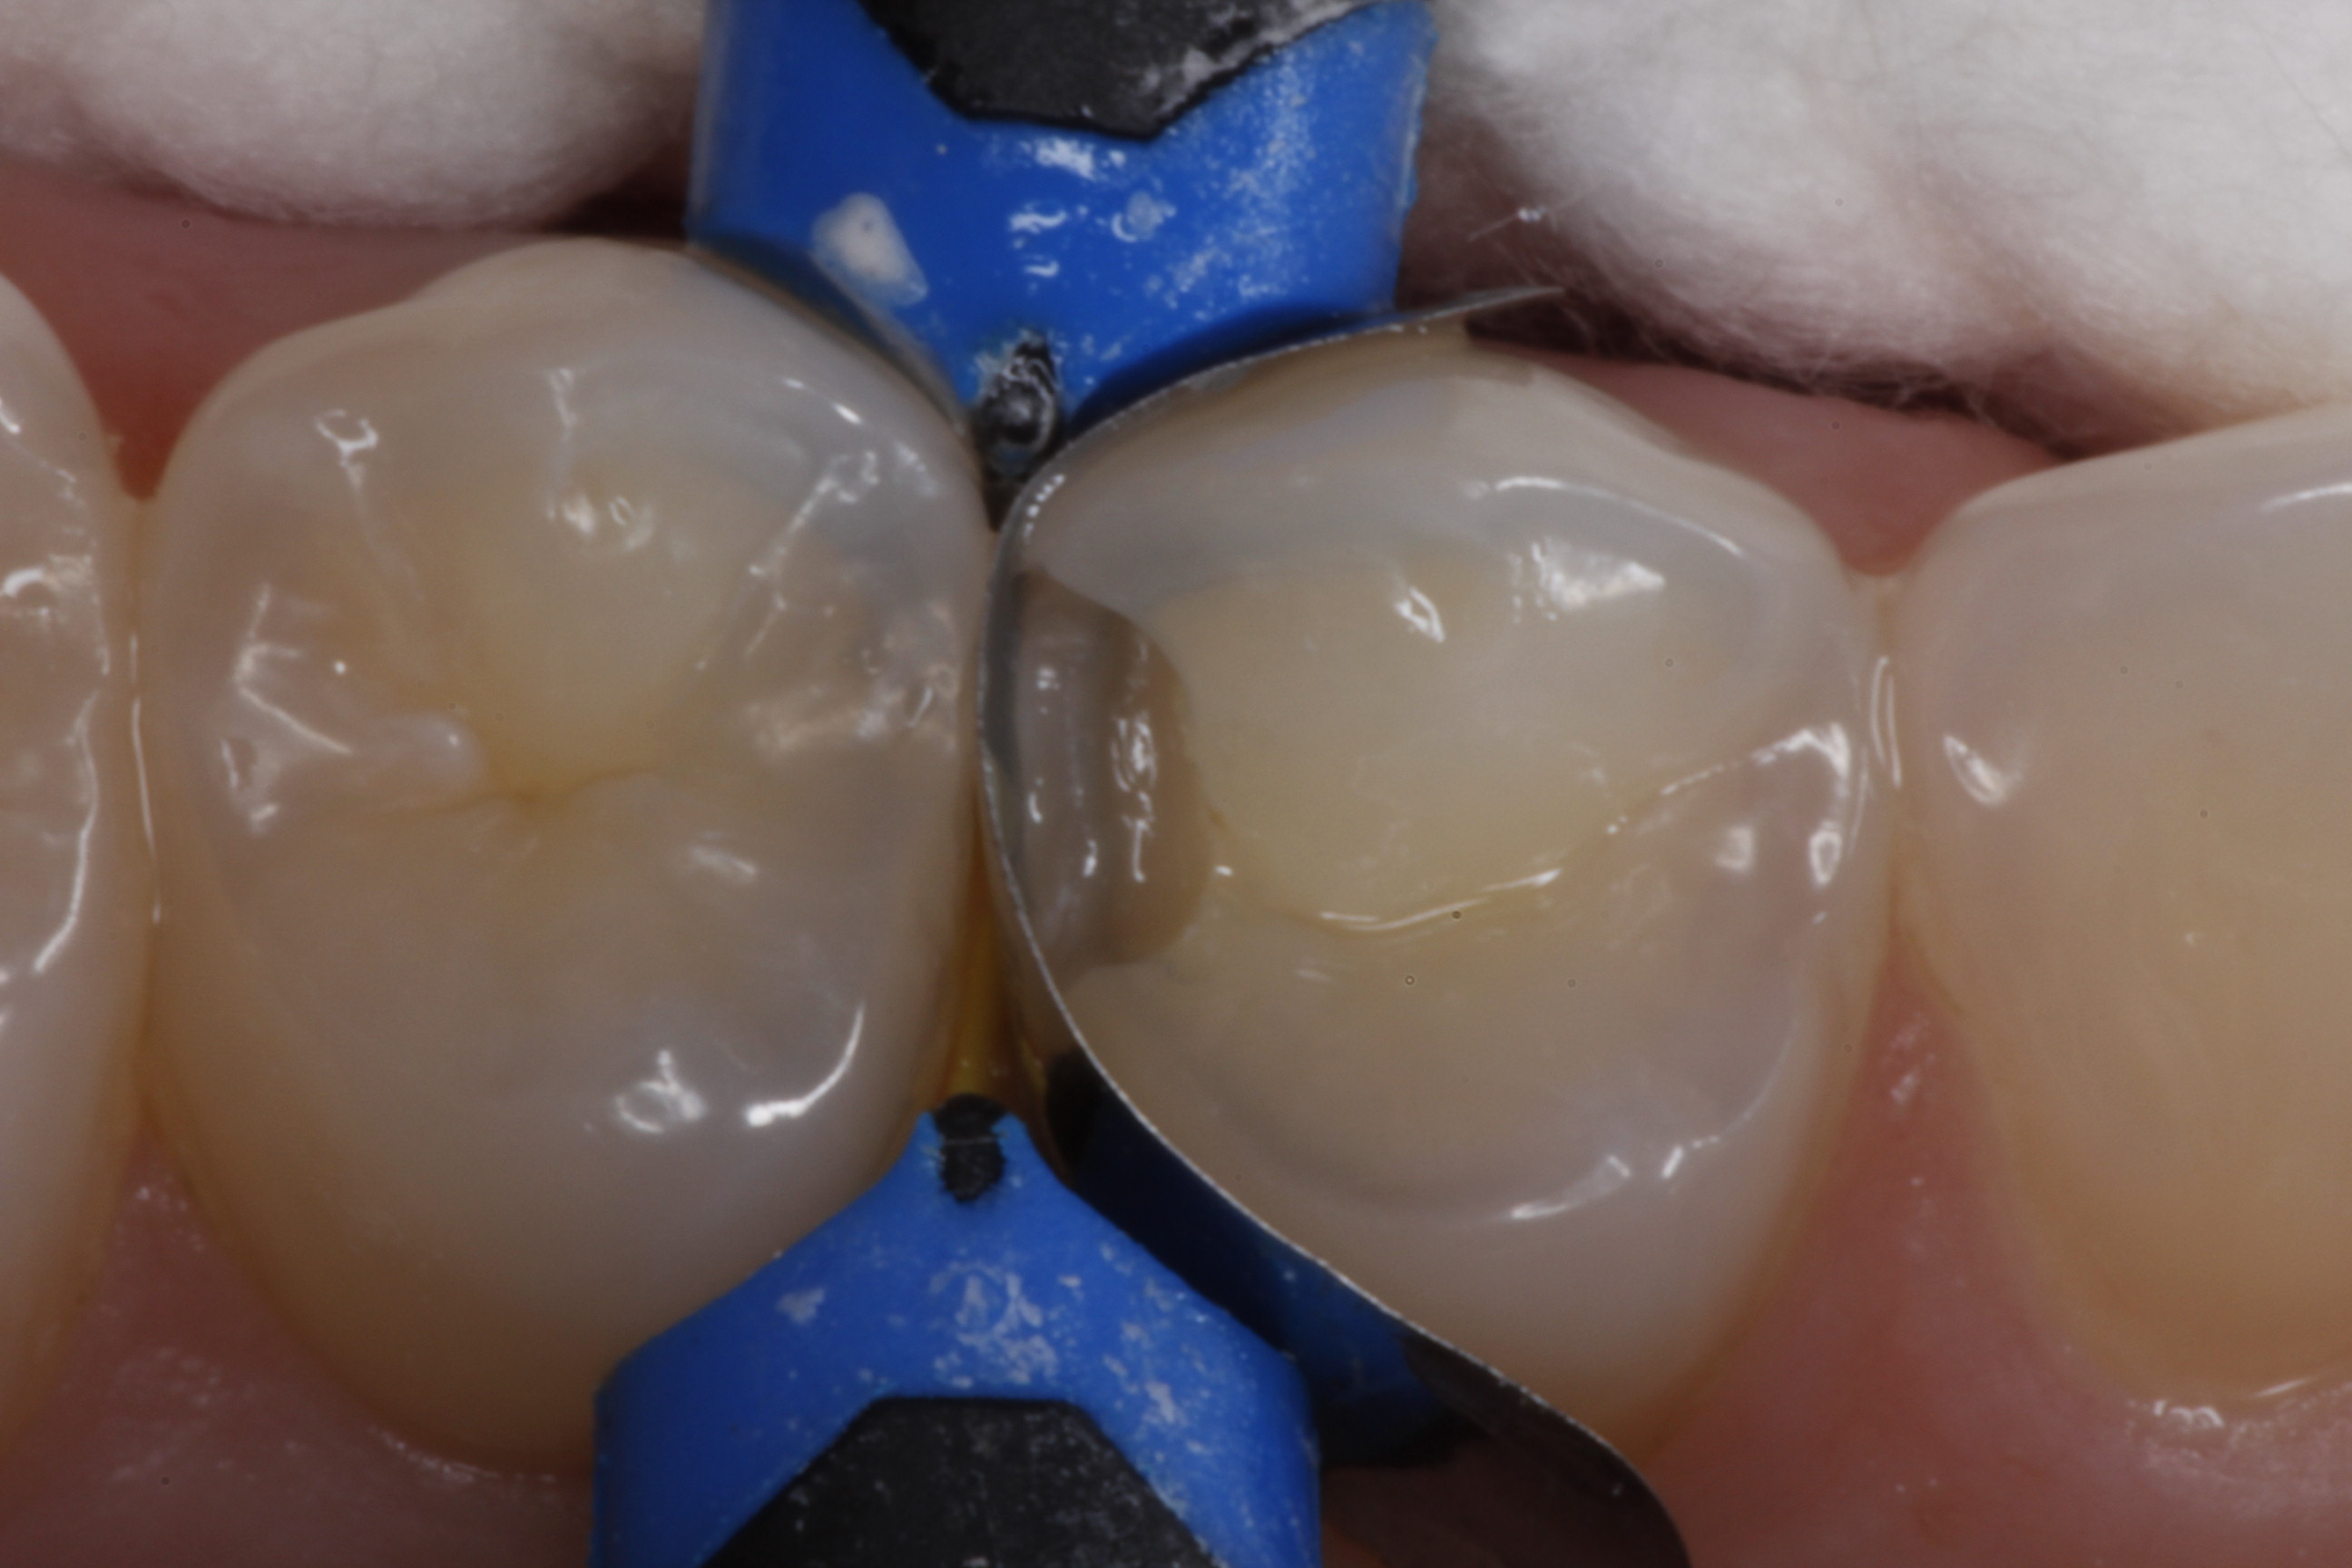

Fig 8. After isolation, a sectional matrix is placed to restore contact and proximal anatomic form to the composite to be placed. The goal is to perform as little rotary finishing and polishing as possible by having the matrix fit precisely to the cavity margins.

Figure 8